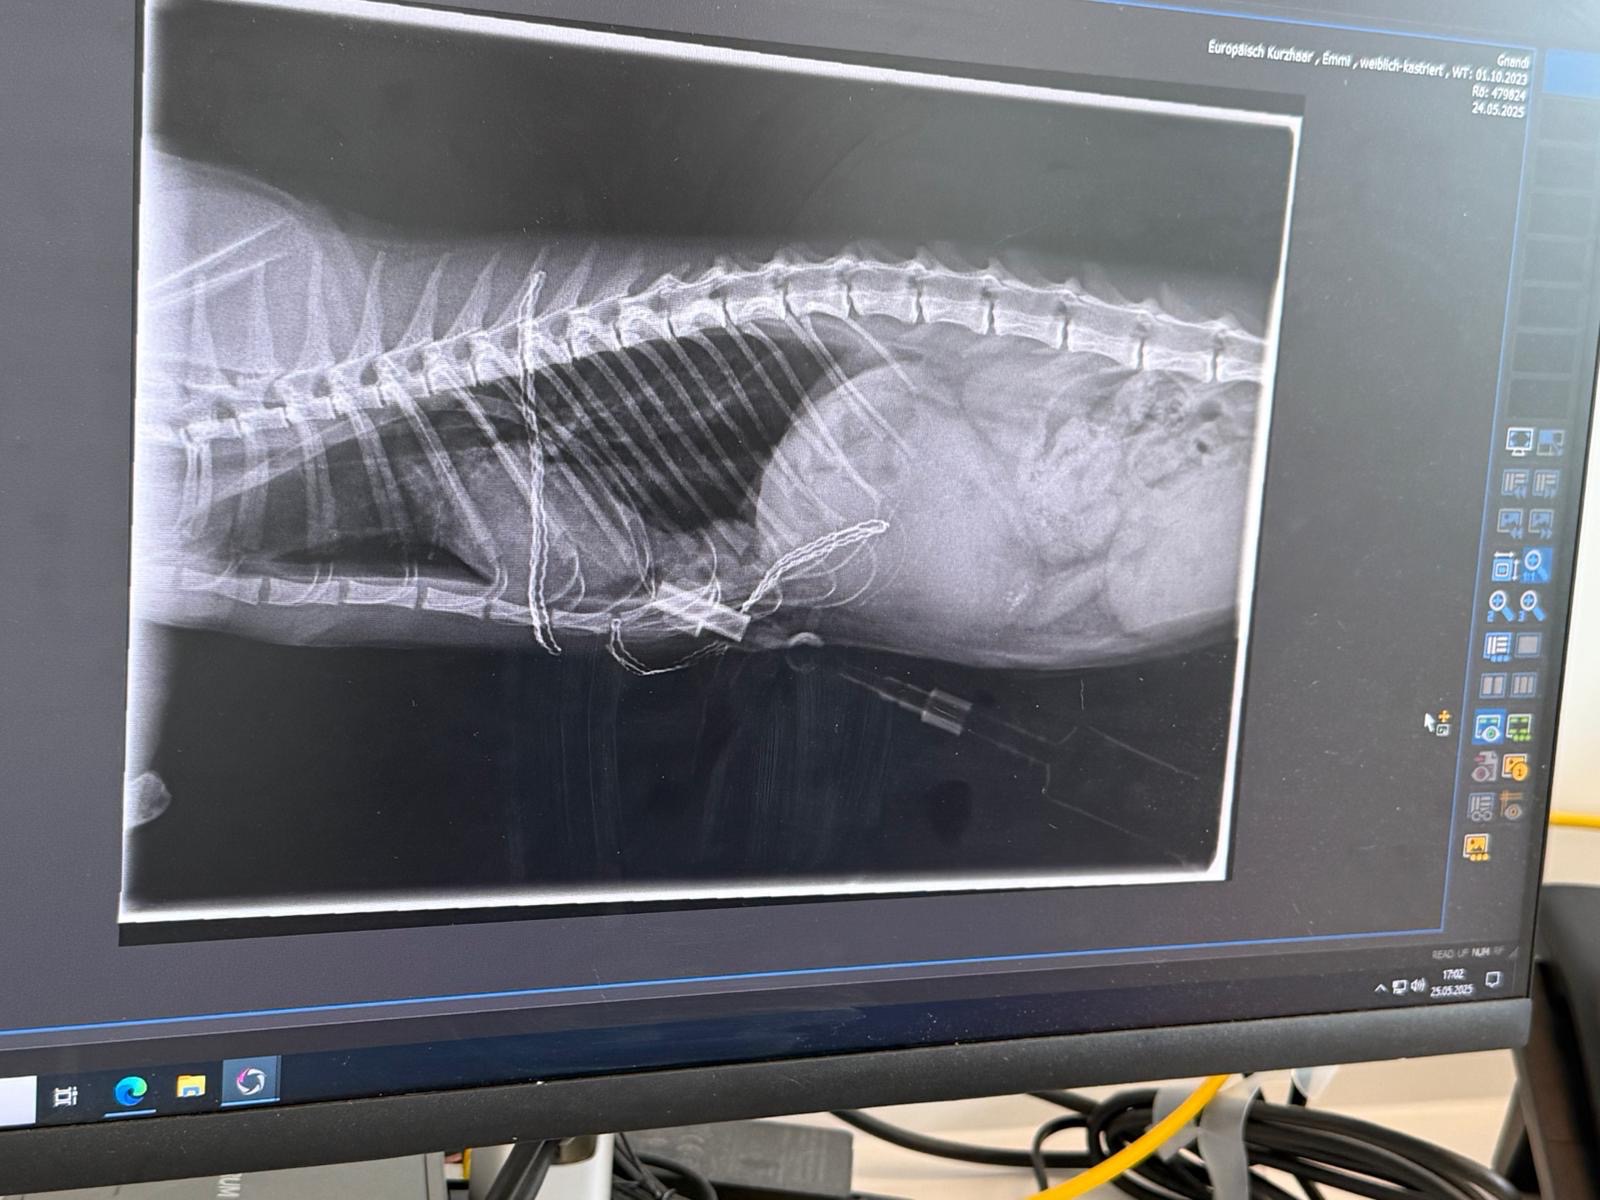

Hallo, das ist eine kurze aber bisher schon sehr harte Geschichte über eine kleine Katze. Emmi ist vor knapp einem Jahr auf einem Bauernhof geboren. Als junges Kätzchen hat sie es geliebt bei den Kühen zu schlafen und hat sich im Stroh versteckt. Als sie dann bei normalen Arbeiten auf dem Hof von einem Traktor Anhänger angefahren wurde musste sie das erste Mal um ihr Leben kämpfen. Doch sie hat es geschafft. Leider konnte sie seit dem Zeitpunkt nicht mehr richtig laufen. Daher hat eine Freundin sie adoptiert. Anfang des Jahres ist dann die Zwillingsschwester von Emmi verstorben. Dann Anfang diesen Monats fing Emmi an zu schwer zu atmen. Anstatt das Besserung eintritt wird es immer schlimmer die Entscheidung steht fest Emmi muss schnellstmöglich in eine Klinik. Die Diagnose: Zwerchfellriss Emmi kämpft bereits das zweite Mal um ihr Leben. Doch wieder einmal schafft sie es sich hoch zu kämpfen. Dann der Schock, die Tierkrankenversicherung übernimmt die Rechnung nicht. 2800€.